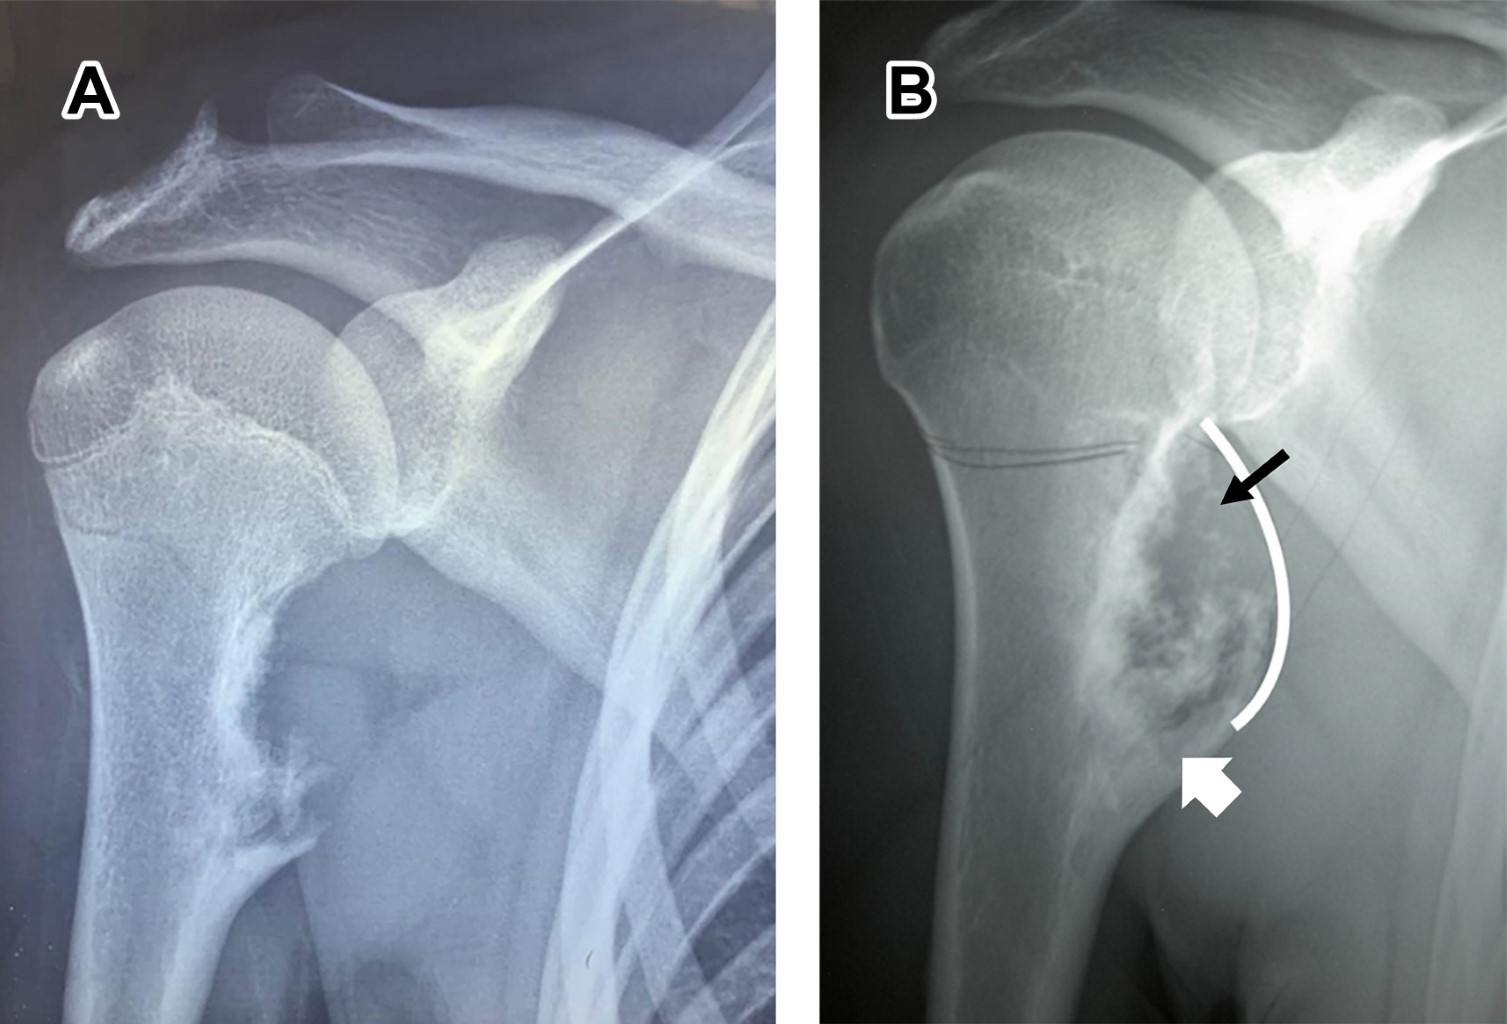

Osteochondroma is a benign tumor, defined as osteocartilaginous exostosis with corticomedullary continuity that reproduces the structure and progression of a physis during growth, considered a developmental disorder rather than a true neoplasia, caused by the separation of a cartilaginous fragment of epiphyseal growth, herniating through the normal bone surrounding the growth plate. It is observed in children and adolescents, without gender difference; most are solitary. The common sites of appearance are the distal end of the femur and the proximal end of the tibia and humerus; it can occur in any bone formed by endochondral ossification.

Figure 1